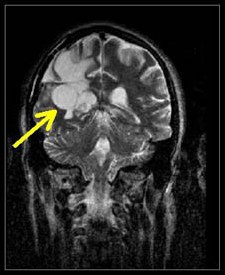

Figure 11.

T2 MRI visualization of a tumor of the brain made possible

by the discovery

of Damadian of the abnormal T2 (and T1) MR (NMR) relaxations

of cancerous tissue.